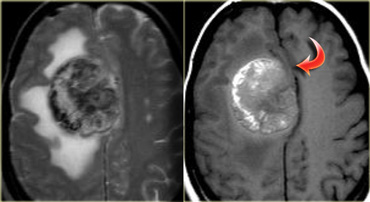

Melanoma metastasis: T2WI and T1WI Melanoma metastasis: T2WI and T1WI

Intra- vs Extra-axial (2)

The differentiation between intra-axial versus extra-axial is usually straight forward, but sometimes it can be very difficult and imaging in multiple planes may be necessary.

The tumor in the case on the left was thought to be a falcine meningioma, i.e. extra-axial and was presented for surgery.

This lesion surely has the appearance of a meningioma: these tumors can be hypointense on T2 due to a fibrocollageneous matrix or calcifications and frequently produce reactive edema in the adjacent white matter of the brain.

However, there is gray matter on the anteromedial and posteromedial side of the lesion (red arrow).

This indicates that the lesion is intra-axial.

If the lesion was extra-axial the gray matter should have been pushed away.

This proved to be a melanoma metastasis.